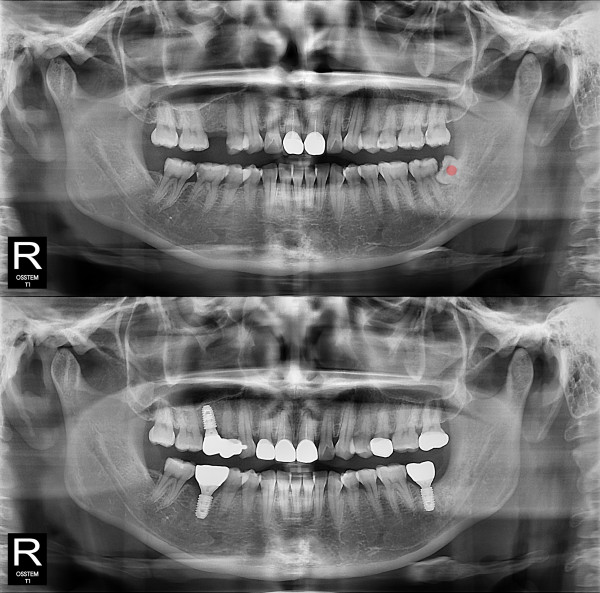

사랑니발치 부분 매복 사랑니

826e40416d712e6cd444a78bde93df4b_1767858248_9482.jpg